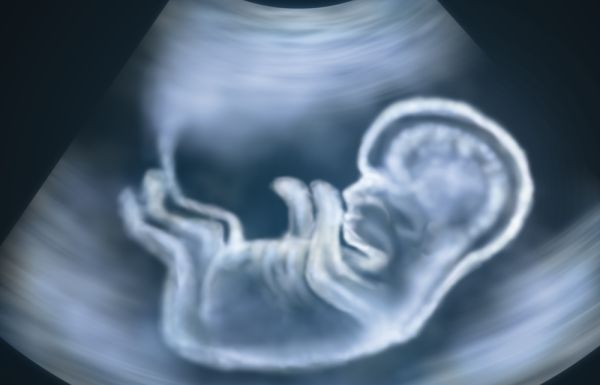

Vlastito mišljenje – život počinje spajanje živih ljudskih spolnih stanica – muške i ženske i njihovom diobom

Moje je osobno mišljenje na temelju životnih spoznaja da zametak nastaje spajanjem živih muških i ženskih spolnih stanica, čime počinje novi život ljudskog zametka i bića, manifestirajući se prvom diobom tih živih stanica. Zametak je od tog trenutka živ, nastao iz ljudskih živih stanica. Meni su te stvari s biološkog stajališta jasne. U tehnike zamrzavanja i odmrzavanja ljudskih spolnih stanica, kao i transplantacije, usađivanja, ne bih ulazio jer o tomu ništa ne znam.